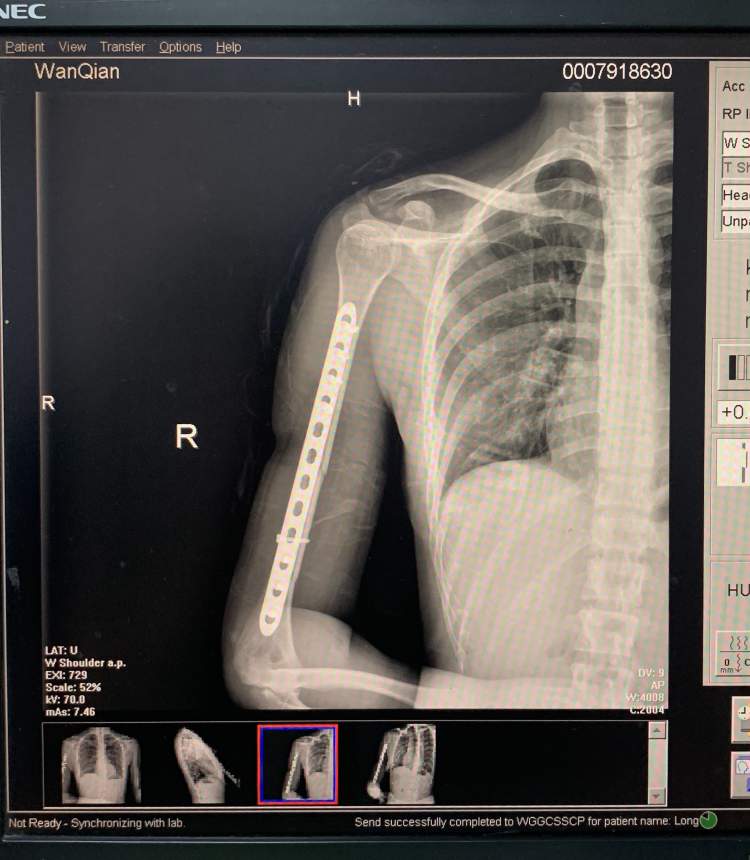

昨天接受采访时,万茜正在接受复健治疗,但她的口气显然比较轻松,调侃自己是“谨遵医嘱,刻苦训练”,“现在右臂里上了钢板,还需要戴护具保护我的手腕,每天坚持在做复健。跳舞的问题,除了右手不能动,身体的其他部分还是活蹦乱跳的,我会努力复健,努力好起来”。

从首次曝光的受伤CT照看,万茜右臂肱骨的粉碎性骨折依然令人心疼,但她调皮地表示,一切还好,可惜最爱的游戏机已经束之高阁,“我一只手咋打游戏,没办法了。”说着,她乐观地透露,疼痛无法避免,现在只能“忍了”,“最多冲个浪分散一下注意力,买买东西,网上逛街,心情会好很多。”